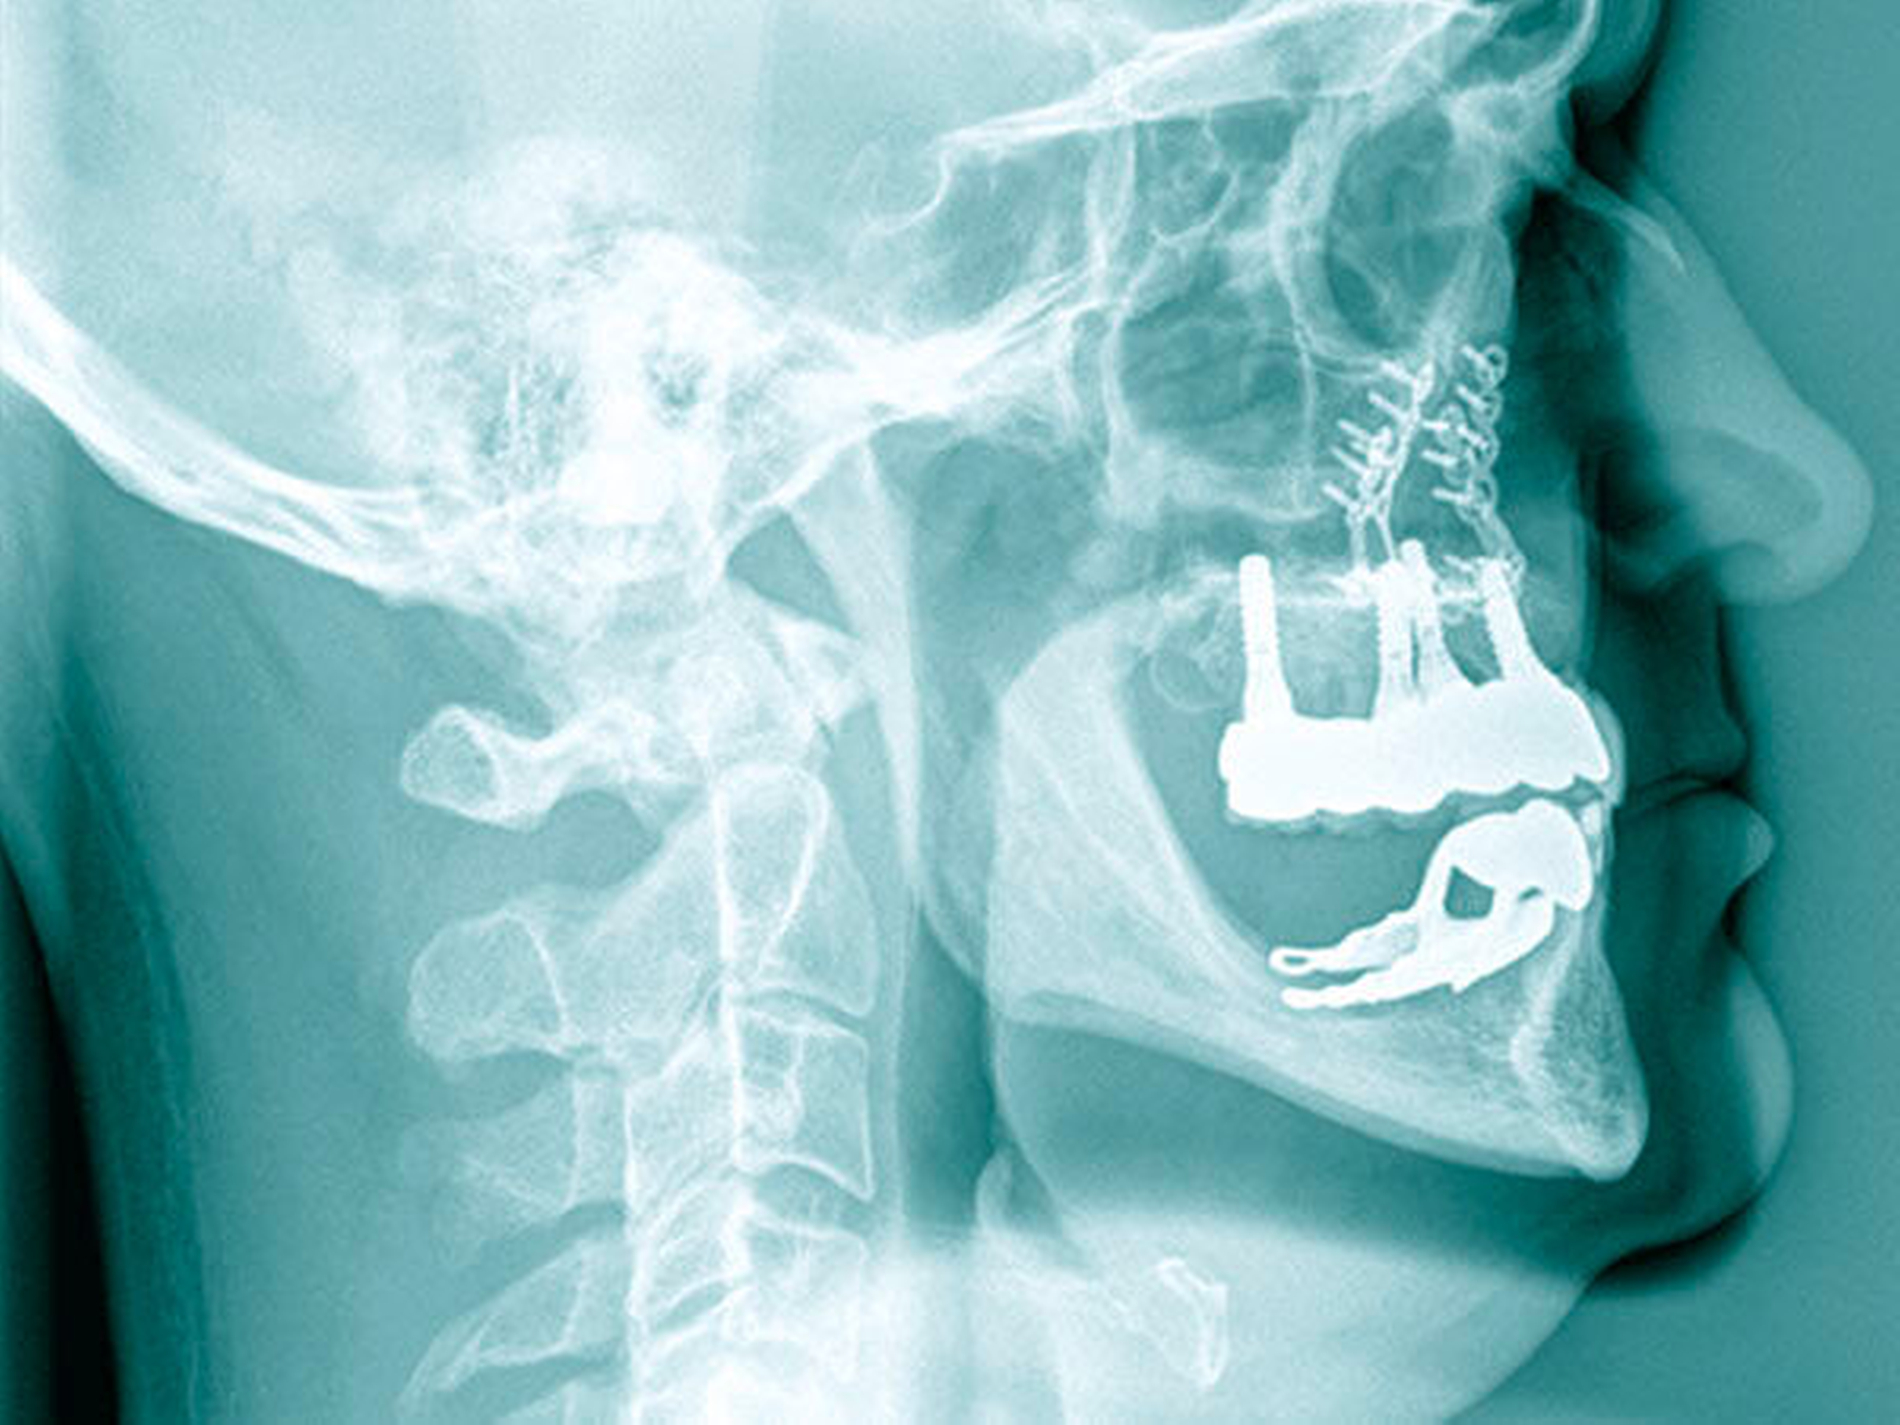

Die klinische Situation zeigte einen atrophierten, teilbezahnten Oberkiefer (herausnehmbarer, nicht implantatgetragener Zahnersatz) sowie einen teilbezahnten Unterkiefer (herausnehmbarer, mit Klammern verankerter Interimszahnersatz) (Abbildung 1). Vor allem fiel der prothetisch eingestellte Kopfbiss im Frontzahnbereich mit ausgeprägter negativer sagittaler Stufe bei einer Rücklage des Oberkiefers von 0,8 cm auf. In der alio loco angefertigten prä-implantologischen Röntgendiagnostik mittels Panoramaschichtaufnahme war dies nicht zu erkennen. Aufgrund des klinischen Bildes eines defizitären Mittelgesichtsprofils erfolgte eine kephalometrische Analyse. Hier bestätigten die ermittelten Werte eine maxilläre Retrognathie (Angle-Klasse III; Abbildung 2).

Insgesamt lag somit eine prothetisch schwierig zu versorgende Situation vor, weshalb nach ausführlicher interdisziplinärer Besprechung gemeinsam mit dem Patienten die Entscheidung zugunsten einer Le-Fort-I-Osteotomie zur Behebung der sklelettalen Fehlstellung und zur Verbesserung des Gesichtsprofils getroffen wurde. Simultan konnten die in situ befindlichen Implantate für den provisorischen Zahnersatz im Sinne eines Operationssplints genutzt werden. Nach der Modelloperation am Artikulator und der Anfertigung sowie der Eingliederung eines individuellen CAD/CAM-gefrästen temporären Zahnersatzes (Poly-Temp®, ceramill®; Amann Girrbach GmbH, Pforzheim, Deutschland) im Oberkiefer (Abbildung 3) erfolgte die maxilläre Umstellungsosteotomie mittels Osteotomie in Le-Fort-I-Ebene. Die temporäre Restauration sicherte intra- und postoperativ die Kieferrelation und Okklusion (Abbildung 4).

Nach unauffälliger Heilung ohne Komplikationen und Korrektur der Kieferrelation (Abbildung 5) konnte die definitive Versorgung (CARES®; Straumann, Basel, Schweiz; Sinfony®, 3M ESPE, Seefeld, Deutschland) drei Monate später eingegliedert werden (Abbildung 6). Im Rahmen der Nachsorgeuntersuchungen (Follow-up aktuell: 2,5 Jahre) zeigten sich stabile Okklusionsverhältnisse bei reizlosem Lokalbefund.